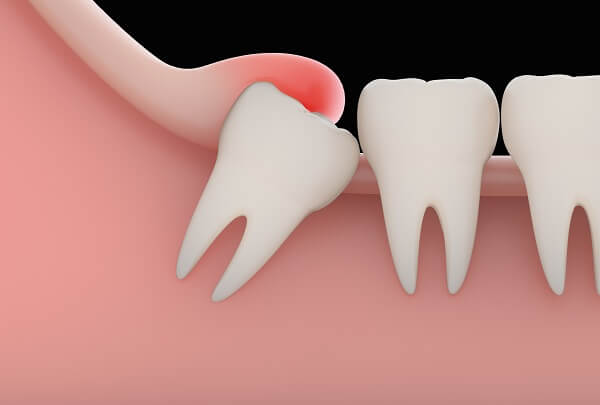

Bạn có tò mò 1 chiếc răng khôn lợi trùm sẽ được xử lý như thế nào? Bác sĩ làm thể nào để nhổ một chiếc răng khôn ra khỏi hàm của bạn? Trong bài viết này chúng tôi sẽ chia sẻ với các bạn cách mà bác sĩ sẽ xử lý 1 chiếc răng khôn lợi trùm.

Cắt lợi trùm răng khôn là một tiểu phẫu trong nha khoa nhằm loại bỏ phần lợi trùm phía trên răng khôn khiến cho răng không thể trồi lên như bình thường. Cắt lợi trùm răng khôn có đau không, khi nào thì nên cắt lợi trùm, cắt lợi trùm giá bao nhiêu thì trong bài viết dưới đây chúng tôi sẽ giải đáp cụ thể cho bạn.

Răng khôn (hay còn gọi là răng số 8, răng hàm lớn thứ 3) là răng mọc cuối cùng trong cung hàm, thường mọc ở độ tuổi 17 - 25. Vì răng khôn mọc muộn nhất nên trong quá trình mọc có thể bị lợi trùm, mọc lệch, mọc ngầm. Răng khôn gây ra nhiều tranh cãi do chức năng của nó không rõ ràng mà lại gây ra nhiều phiền toái.